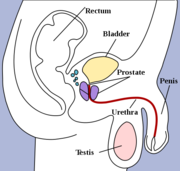

| 1. 6. 2011, 07:25 | Prostata.jpg (soubor) |  | 96 kB | Webmaster | (Zdroj: http://en.wikipedia.org/wiki/File:Prostatelead.jpg) | 1 |

| 15. 5. 2011, 12:47 | Penis.png (soubor) |  | 76 kB | Webmaster | 1 | |